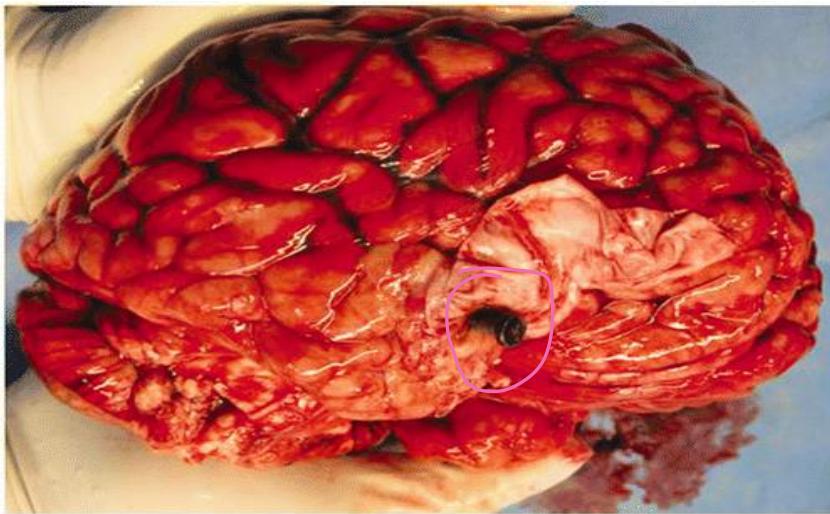

- Brain Contusion:

- Description: Contused Wound accompanied with severe skull fracture. Brain Contusion.

- Finding: Brain tissue protrusion, characteristic tissue loss